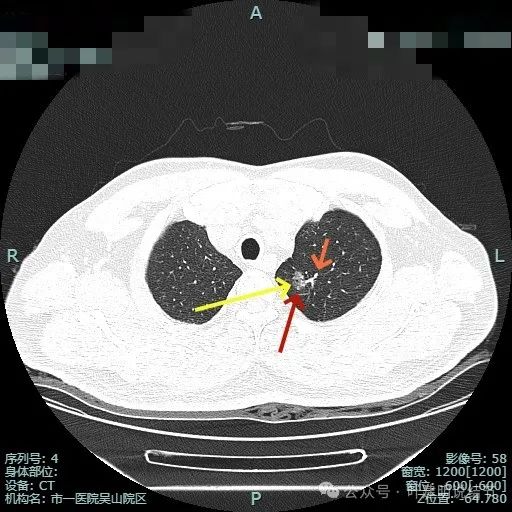

先看非薄层影像:

左上病灶出现,密度较淡,但轮廓较清。

密度不纯,有明显分叶。

有血管异常增粗与进入,边缘有细毛刺征。

血管穿行与表面浅分叶。